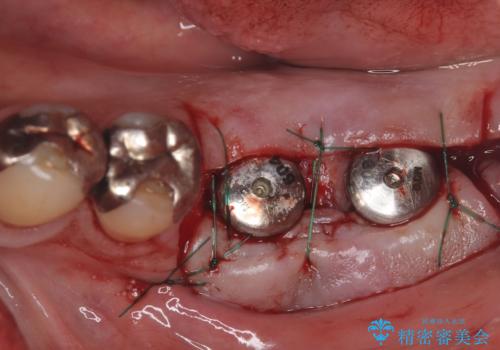

今回の治療では、まず左下6番と7番の欠損部に、骨の状態を考慮しながら慎重に2本のインプラントを埋入しました。インプラント体と骨がしっかりと結合するのを待った後、最短の期間で最終的な被せ物を装着するための精密な型取りを実施。最終的に、周囲の歯と調和した審美性の高いセラミック製の歯を装着しました。